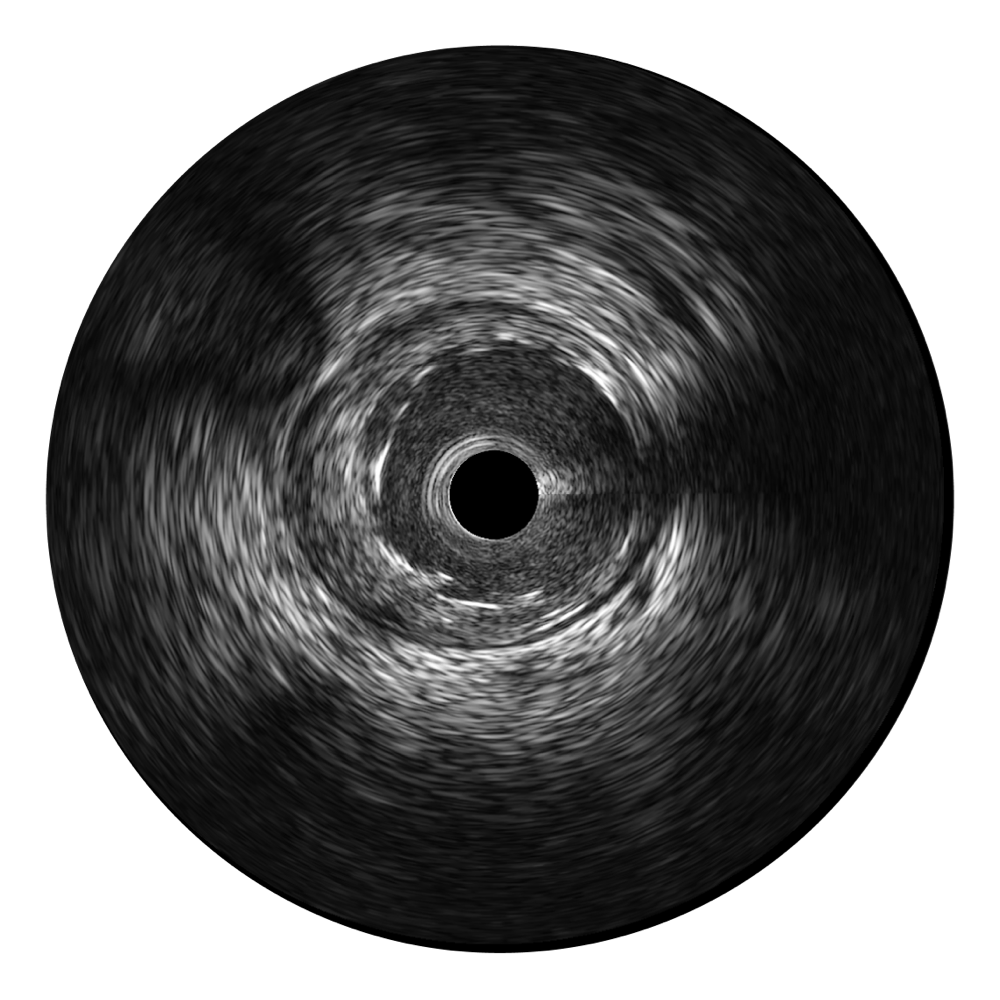

• 美狮贵宾会官网宽频IVUS图像

对比传统IVUS导管成像,美狮贵宾会官网宽频IVUS图像的近场支架梁显影更细腻,远场中膜外血管仍清晰可辨,兼顾远中近,兼顾分辨力与穿透深度